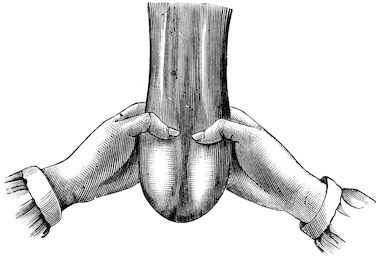

| Bistournage | 751 | |||

| Martelage | 756 | |||